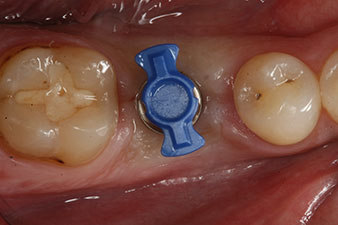

El torque en el momento de la carga mecánica fue de 43 Ncm. Asimismo, después de atornillar un poste de medición especial adaptado al sistema de implante (SmartPeg), el valor ISQ se determinó con la sonda del módulo Osstell ISQ de W&H.

Este módulo Osstell ISQ que se encuentra disponible como accesorio para la unidad Implantmed de W&H y se acopla al motor de implantes (véase figura 11). El valor ISQ adimensional fue de 64 justo en el momento de la inserción en la dirección bucovestibular y de 68 en la dirección mesiodistal (valor máximo = 100).

Este habría permitido una cicatrización abierta o incluso un tratamiento inmediato. Sin embargo, como no se disponía de suficiente hueso en la parte crestal del implante, el área se aumentó con las virutas óseas recopiladas durante la preparación del lecho del implante y se suturó para que no penetrara saliva.